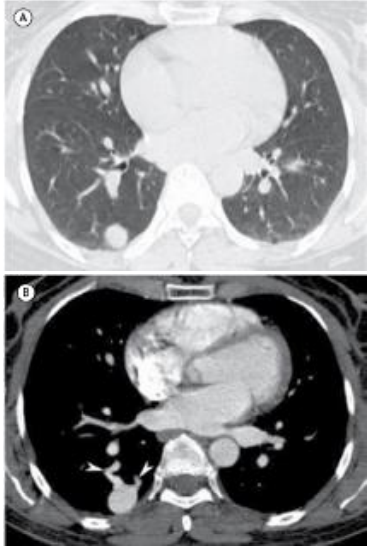

Mulher, 37 anos, queixando-se de tosse e febre há três dias. A paciente realizou tomografia computadorizada como parte da rotina diagnóstica.

Em relação ao exame apresentado, assinale a afirmativa correta.